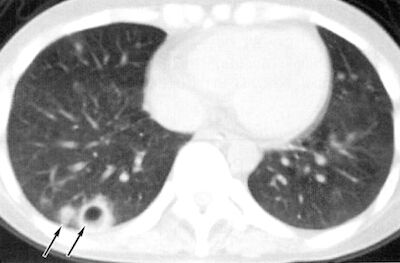

敗血症 性 肺 塞栓 症 画像. 敗血症性肺塞栓症septicpulmonaryembolism以 下SPEは細菌に汚染された栓子による肺塞栓と栓子 による肺感染症からなる比較的稀な疾患である原因と しては感染性心内膜炎血栓性静脈炎腎膿瘍肝膿瘍. 敗血症性肺塞栓症 Septic Pulmonary EmbolismSPE とは 細菌塊が肺動脈に塞栓を起こし結果として 肺梗塞局所的な膿瘍を生じるもの 疾患の頻度は低く症状は非特異的なため 診断が遅れることが多い CHEST 2005. 目次1 敗血症性肺塞栓症septic pulmonary embolizationSPESEとは11 敗血症性肺塞栓症の画像所見2 Lemierre症候群3 ご案内31 腹部画像診断を学べる無料コンテンツ3.

敗血症性肺塞栓症septic pulmonary embolismSPE 自分は空洞化をみたらこの6つを念頭に考えていきます この空洞形成というのは本当にすごいメカニズムでぜひとも知ってもらえると嬉しいです. を要したと報告されています 肝臓49巻3号101-1072008 肝膿瘍の死亡率は 肝膿瘍の原因が細菌性の場合敗血症性ショックdic などにより死亡した症例が14と報告されています 肝臓49巻3号101-1072008. ブリタニカ国際大百科事典 小項目事典 - 肺真菌症の用語解説 - 真菌による肺感染症で人間の真菌症のうち最も発生頻度の高いもの内因性のカンジダ症放線菌症ジオトリクム症外因性のものではアスペルギルス症クリプトコックス症ノカルジア症などがある.